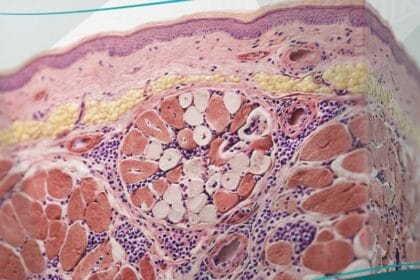

يُعرف كسر الإجهاد طبياً بأنه كسر شعري دقيق يحدث في العظم نتيجة تعرضه لقوى فيزيائية متكررة تفوق قدرته الطبيعية على التحمل والترميم الذاتي المستمر.

وفقاً لـ “موقع حياة الطبي“، فإن هذه الحالة تحدث عندما تفشل العضلات المحيطة بالعظم في امتصاص الصدمات الناتجة عن النشاط البدني، مما ينقل العبء مباشرة إلى النسيج العظمي الصلب.

تؤدي هذه الضغوط المستمرة إلى إحداث اختلال في التوازن بين عملية هدم الخلايا العظمية القديمة وبناء خلايا جديدة، وهو ما يُعرف في الفسيولوجيا الرياضية بدورة إعادة تشكيل العظام الهيكلية.

- مرحلة الالتهاب (أيام 1-5): تبدأ فور حدوث الشق المجهري، حيث تتجمع الصفائح الدموية لتكوين جلطة دموية أولية توفر إطاراً للترميم.

- مرحلة الدُشبذ اللين (أسابيع 2-3): يبدأ الجسم في إنتاج الغضاريف والأنسجة الليفية لربط طرفي الشق في كسر الإجهاد.

- مرحلة الدُشبذ الصلب (أسابيع 4-12): يتم استبدال النسيج اللين بعظم صلب (عظم منسوج) يمكن رؤيته بوضوح في الأشعة السينية في هذه المرحلة.

- مرحلة إعادة التشكيل (شهور إلى سنوات): يستمر الجسم في نحت العظم الجديد ليأخذ شكله الطبيعي الأصلي ويستعيد قوته الميكانيكية الكاملة.